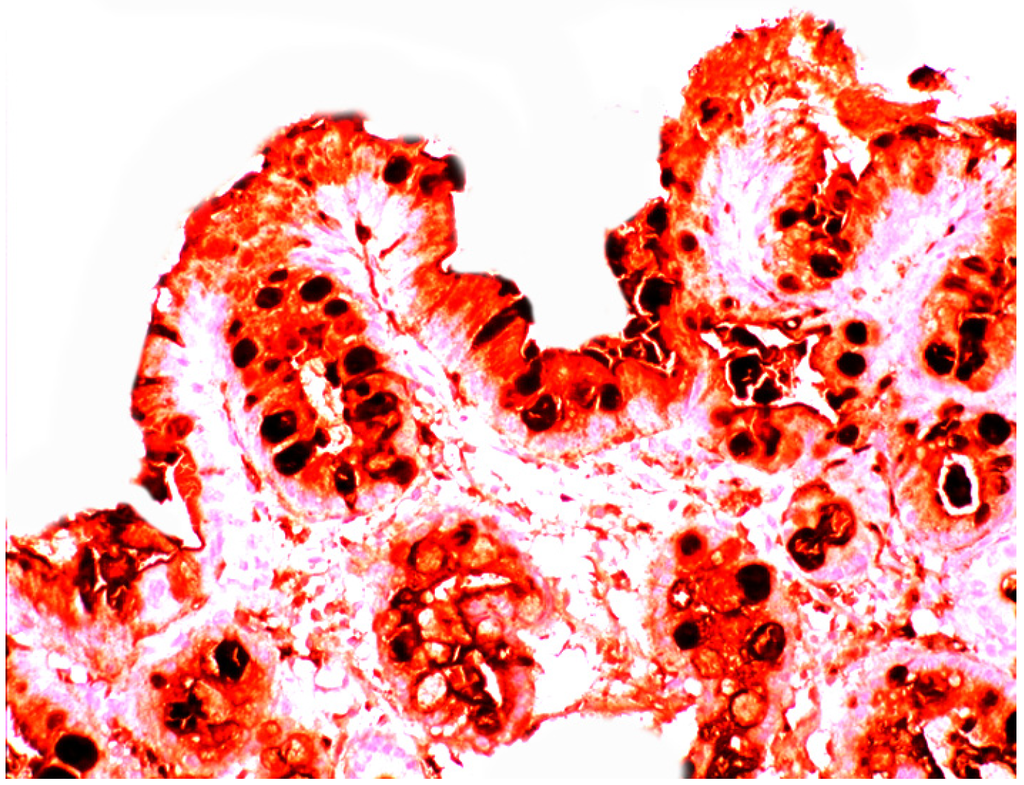

In active ulcerative colitis, lysozyme is up-regulated in metaplastic Paneth cells (left colon) and in the deep half of the crypts (Figure 14). In ulcerative colitis in remission, lysozyme is up-regulated in metaplastic Paneth cells [9] (left colon, Figure 15). No lysozyme expression is recorded in the crypts. In Crohn’s colitis lysozyme up-regulation is found in metaplastic Paneth cells (left colon), in the crypts as well as in the lamin propria mucosae [9] (Figure 16). The increased lysozyme production in the colonic mucosa in patients with inflammatory bowel disease may highlight an amplified mucosal protection against the pathogenic bacteria proliferating in the colonic microenvironment in these patients [70,71,72,73,74,75,76,77,78,79,80,81].

Figure 16.

Crohn colitis: Marked lysozyme immunoreactivity in macrophages in the lamina propria and in epithelial cells at the bottom of the crypts (lysozyme immunostain, ×20).